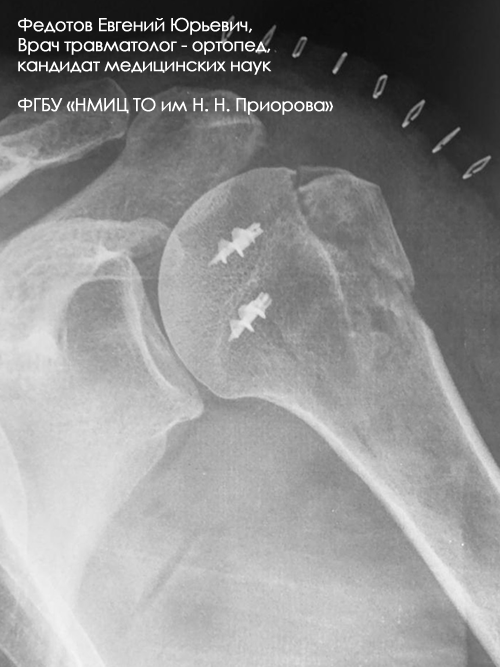

Закрытый многооскольчатый внутрисуставный со смещением перелом проксимального отдела плечевой кости.

Операция: открытая репозиция отломков проксимального отдела плечевой кости, накостный остеосинтез пластиной и винтами